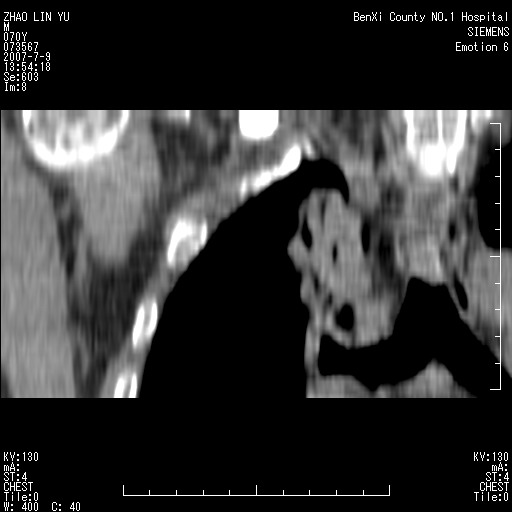

以下是引用王靖旗在2007-7-10 17:12:00的发言:[br] 男、70、咳嗽两个月,半年前换瓣手术,胸片未见异常,于昨天行x片发现右肺上野大片影,行ct扫描,这里是减薄图像,余肺正常。明天晚上会有增强扫描片,到时我会上传。[br][br] 冠状位请大家细看,应该是有意义的,[br][br] 请大家先看平扫发表意见。[br][br]

[br]冠状面[br]

以下是引用zhangzhongshou在2007-7-10 21:43:00的发言:[br]右肺上叶周围型肺癌,以孤立型细支气管肺泡癌可能性大。